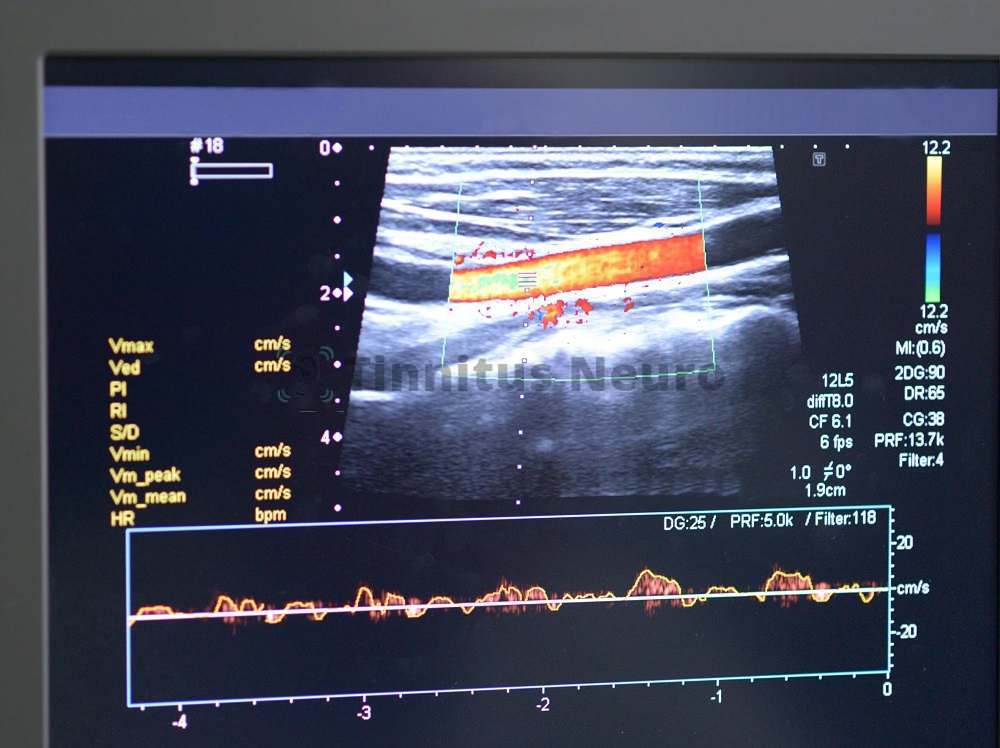

Допплерография

Благодаря использованию специальных датчиков, врачи могут получить ценную информацию об артериальном кровоснабжении отдельных участков головного мозга, характеристиках венозного оттока от тканей центральной нервной системы.